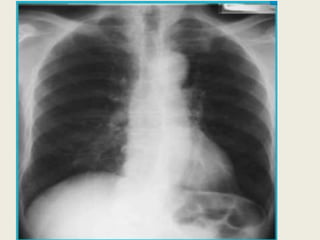

Radiologic Findings

Chest radiograph

• Normal

• Hyperinflation

– Increased anteroposterior diameter

– Translucent (dark) lung fields

– Depressed or flattened diaphragm